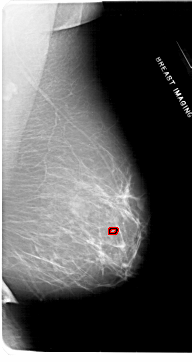

A_1953_1.RIGHT_MLO

RIGHT_MLO LINES 6871 PIXELS_PER_LINE 3631 BITS_PER_PIXEL 12 RESOLUTION 43.5 OVERLAY

FILE: A_1953_1.RIGHT_MLO.OVERLAY

TOTAL_ABNORMALITIES 1

ABNORMALITY 1

LESION_TYPE CALCIFICATION TYPE PLEOMORPHIC DISTRIBUTION CLUSTERED

ASSESSMENT 4

SUBTLETY 1

PATHOLOGY BENIGN

TOTAL_OUTLINES 1

BOUNDARY